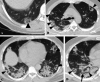

Is target sign (bull’s eye appearance) associated with adverse outcomes in COVID 19 patients? A case series and literature review

Background: In COVID-19 pneumonia, chest CT scan plays a crucial role in diagnosing and closely monitoring lung parenchyma. The main reportedly chest CT features of novel coronavirus pneumonia (NCP) have been fully discussed in the literature, but there is still a paucity of reports on uncommon CT manifestations.

Case presentation: Herewith, we have reported ten rRT-PCR confirmed COVID-19 patients with CT target signs (bull's eye appearance); additionally, we have reviewed previously reported cases. Reviewing the literature, we found eight COVID-19 patients with target sign in the literature. 18 patients were included with a median age of 43. 11 (61%) patients were males. In 87% of patients, the lesions developed within the second-week post symptom onset. These patients mostly experienced an extended hospital stay (median = 10 days), with 53.8% of cases being admitted in ICU. The in-hospital mortality rate was 23%.

Conclusion: Our findings indicate that lesions with a bull's eye appearance are not significantly associated with higher mortality in hospitalized COVID-19 patients.